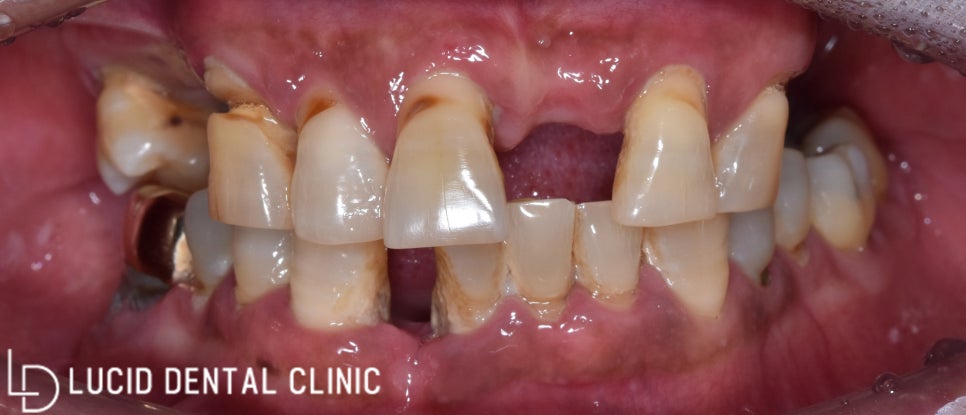

"어금니가 없어서 식사가 힘들어요.

남은 치아까지 흔들리거나 패여서

예쁘지도 않고... 해결할 수 있을까요?"

어느 날, 한 환자께서 위와 같은 고민으로

논현역 루시드 치과 에 방문하셨습니다.

심미성을 중요시하는 앞니와는 다르게

어금니는 저작 기능을 위주로 하고 있는데요.

이런 저작 기능을 잃은 채

힘들게 식사하신다고 하셔서

걱정되는 마음에 얼른

구강 검진을 시행해 봤습니다.